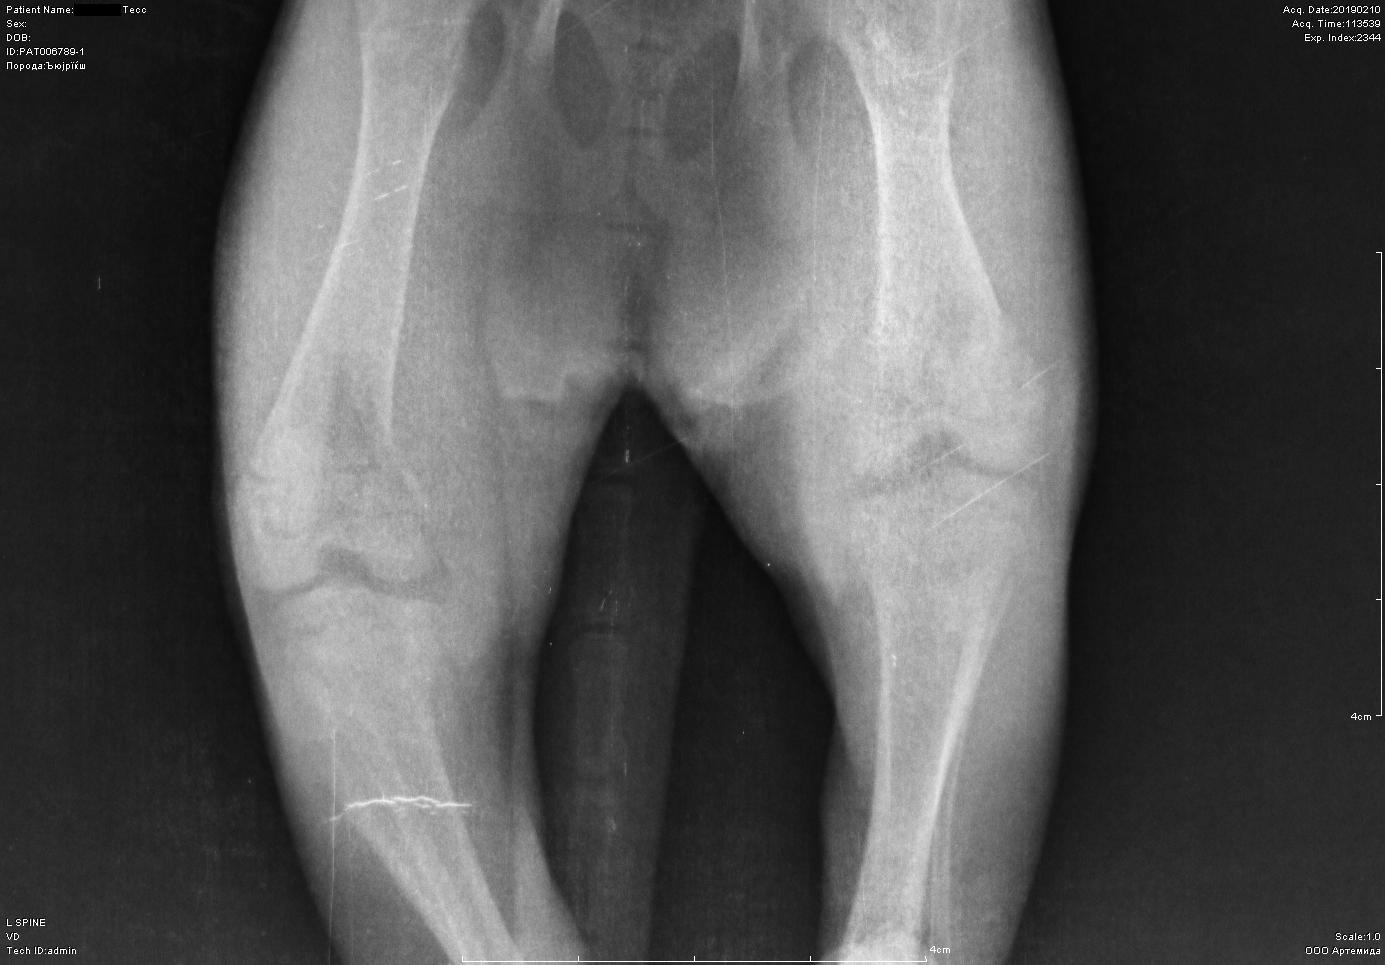

Рентген котенка

Добрый день. Котенок рожден 5 ноября 2018 года, девочка, не привита. Проглистована. Неожиданно в один момент стала припадать на задние ноги. Как бы бережет их и старается не прыгать лишний раз. Свозили два дня назад к ветеринару - всю её прощупал, говорит переломов нет, вывихов тоже. Сделали блокаду ближе в крестцу новокаина, чтобы снять симптомы. Прописал кальций в таблетках Ексел. Сейчас всё примерно так же - лапки задние бережет, но стала по активнее. Прошу специалистов, если такие тут бывают, оценить снимки, т.к. врач ещё кое-что сказал и хотелось бы услышать ваше мнение. Скан расшифровки и д/з потом приложу.

Фронтальная проекция